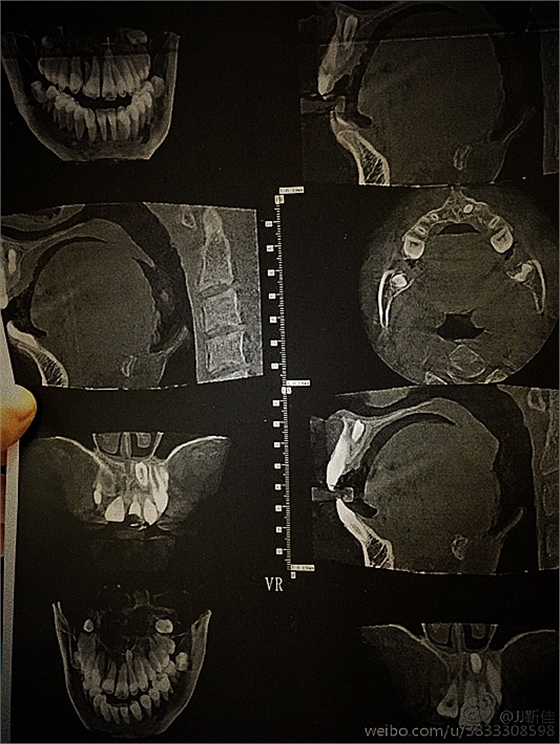

ct定位